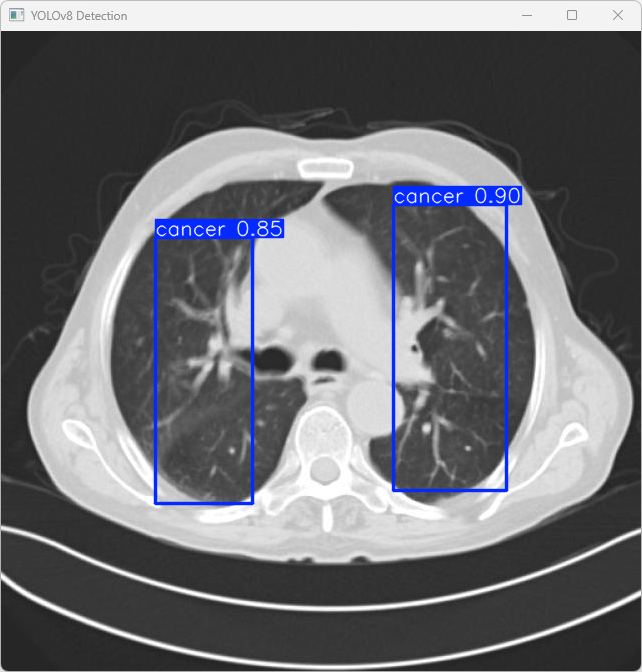

执行imgTest.py代码后,会将执行的结果直接标注在图片上,结果如下:

这段输出是基于YOLOv8模型对图片“imagetest.jpg”进行检测的结果,具体内容如下:

图像信息:

(1)处理的图像路径为:TestFiles/imagetest.jpg。

(2)图像尺寸为640×640像素。

检测结果:

(1)2 个 cancer(肺癌)

处理速度:

(1)预处理时间: 6.0 毫秒

(2)推理时间: 5.1 毫秒

(3)后处理时间: 94.9 毫秒

总结:

该模型能够快速处理医学影像数据,并在短时间内给出诊断结果,显示了其在医学影像自动诊断系统中的应用潜力。